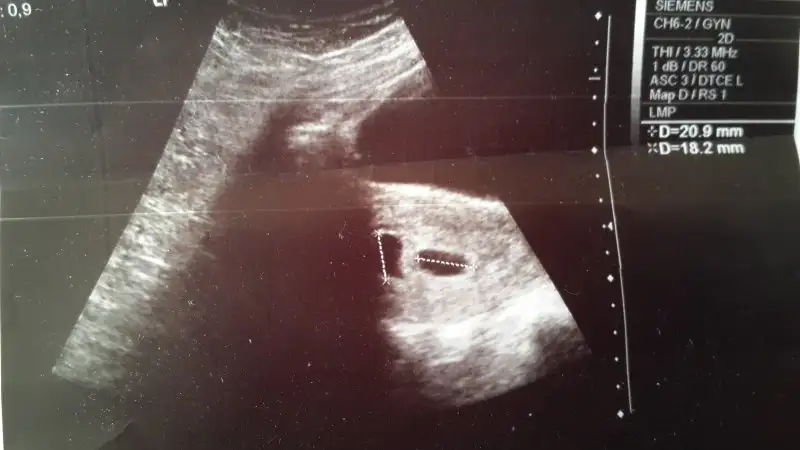

Havalianne__ ya hala düşünüyorum acaba doktorun yanılıyor mu? Sana hiç mi göstermedi bak şu üç çizgi bu ölçümleri fln demedi mi? Herşeyin erkek olarak gösteriyor bide renkli usg de bariz bir şişlik var çok ilginç

benim kardeşime de ultrasonda kız dediler ama erkek dogdu gerçi 25 yıl oldu ama... herşeyi pembe kırmızıydı garibimin...Yok göstermedi cnm,bende bidaha sormadım tadı kaçtı artik.2 3 seferdir kız dedi ama bak su üç çizgisi genital organı falan diye söylemedi,inş yanılıyordur:)sormayacam artık 2 ay kaldı doğuma zaten,canlı gorecem.eğer gerçekten kız olarak doğarsa hicbir teoriye inanmicam.